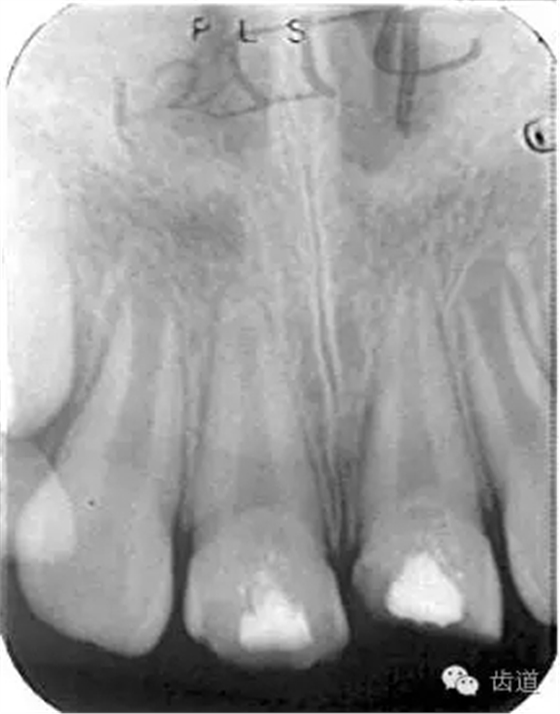

1.術(shù)前X線片

術(shù)后

術(shù)前

術(shù)后199日

術(shù)后1084日